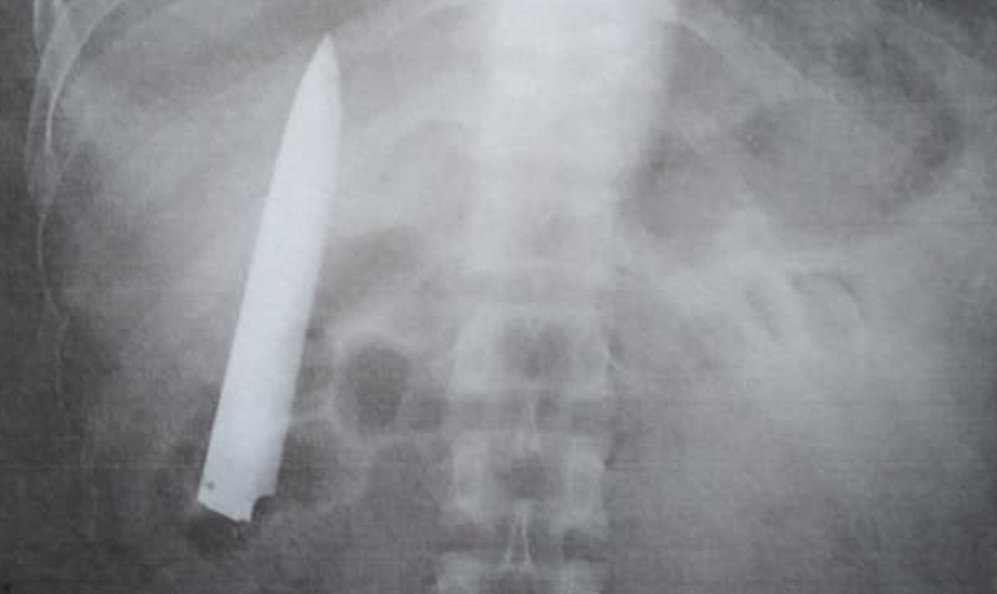

▲男一年後才發現體內有刀。(圖/翻攝自Facebook/Kent Ryan)

菲律賓36歲男子肯特(Kent Ryan Tomao)去年下班路上遭人刺傷,醫生只簡單縫合傷口就讓他回家,沒想到14個月後做X光檢查意外發現,體內竟然藏有一把長達10公分的刀,而且只差幾公分就有可能刺穿肺部。

來自基達帕萬市(Kidapawan)的肯特,因為礦場公司要求員工做健康檢查,才發現去年1月遭到攻擊的刀片一直留在體內,他憤怒表示,「我現在才知道,為什麼天氣一冷胸口就會疼痛,我不知道體內有刀,且疼痛感沒有很嚴重,所以就沒有再去看醫生,現在總算知道真正的原因」。

肯特體內的刀由於十分靠近肺部,需要緊急進行手術不然可能會有生命危險,然而無力支付醫療費用的他,不打算對原本的醫院提告,只希望他們能夠幫助他免費取出這把刀,好讓他可以再回去工作。